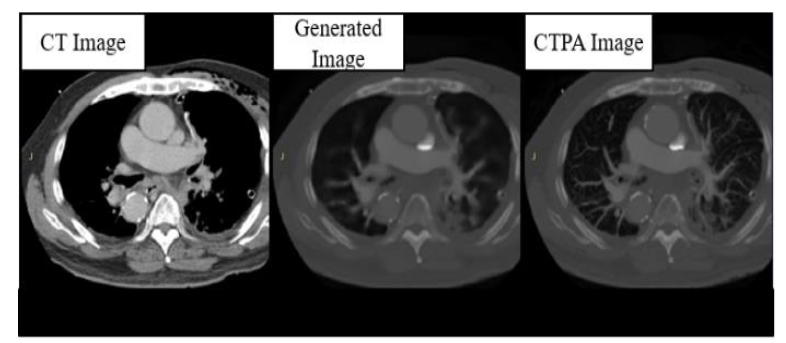

In the CTPA_CycleGAN model, as shown in

, we used U-Net and ResNet as the backbone of the network for training, and we can see that the performance on U-Net is not as good as expected, although the restoration performance on bones and organ tissues is excellent as in the CTPA_Pix2pix model, but the microvascular part of the lungs The generation of the lung microvasculature was different. In the CTPA_CycleGAN model (U-Net), the amount of vessel restoration was improved, but the main pulmonary artery was not generated, making the vascular trend different from reality and making it difficult to identify the symptoms of PE.